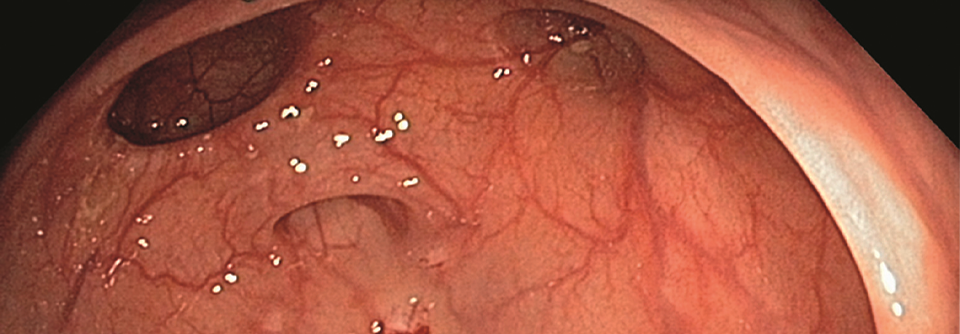

Divertikel im Dünndarm sind eher selten und bleiben meist klinisch stumm. In einigen Fällen führen sie jedoch zu abdominellen Beschwerden und Komp­likationen. Bei akuten klinischen Symptomen sollte daher auch an eine Dünndarmdivertikulose gedacht werden.

Die Dünndarmdivertikulose tritt mit einer Prävalenz von bis zu 1,3 % und vor allem bei Männern zwischen 60 und 70 Jahren auf. Am häufigsten finden sich die Divertikel im Duodenum, in etwa jedem vierten Fall im Jejunum und zu 5–10 % im Ileum. Als Ursache wird vermutet, dass die Peristaltik des Dünndarms gestört ist und spas­tische Kontraktionen zu Schwachstellen in der Darmwand führen, schreiben Dr. Hélène Gros und Dr. Benjamin Wagner vom Stadtspital Triemli in Zürich. Meist bleiben die Divertikel asymptomatisch. Treten Beschwerden auf, sind diese mit Obstipation, Blähungen und unklaren Abdominalschmerzen oft unspezifisch. 10–30 % der Patienten entwickeln Komplikationen wie eine Divertikuliti…